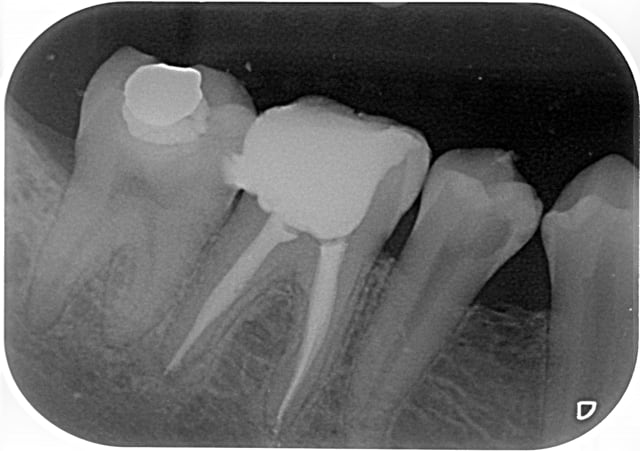

petit jeu:

A vous de trouver quelle endo a été faite au thermafill et laquelle au gutta condensor?

Endo 2 : Thermafil

En général le thermafil est moins radioopaque que la gutta thermocondensée, donc j'aurais plutôt dit la 1, mais c'est vrai que sur la 2 tu as probablement quatre canaux, ce qui augmente la densité et les bouts font un peu "pointu" laissant penser que les tuteurs se sont peut être un peu décalés...

Allez je joue:) sans être sure,mais je dirais

1/Thermafill( on croit apercevoir les tuteurs)

2/gutta condensor ,( je crois voir une spirale dans l' un des canaux mesiaux! )

1:thermafill

Et bien je vois que tout le monde n'est pas d'accord...

endo1 a été fait au gutta condensor

endo 2 au thermafil.

Seul Marc a eu du nez la dessus. ;-)

Comme quoi, radiologiquement, difficile de faire le distinguo entre ces deux méthodes.

C'est la rectitude de l'obturation dans le dernier millimètre apical, surtout sur le canal distal qui m'a mis sur la voie.

Image 1 thermo condensation.

La compression de la technique a provoqué la fusée au niveau de la racine distale de 36.

image 2 thermafil

Je crois apercevoir la pointe du tuteur thermafil sur racine distale de 46.